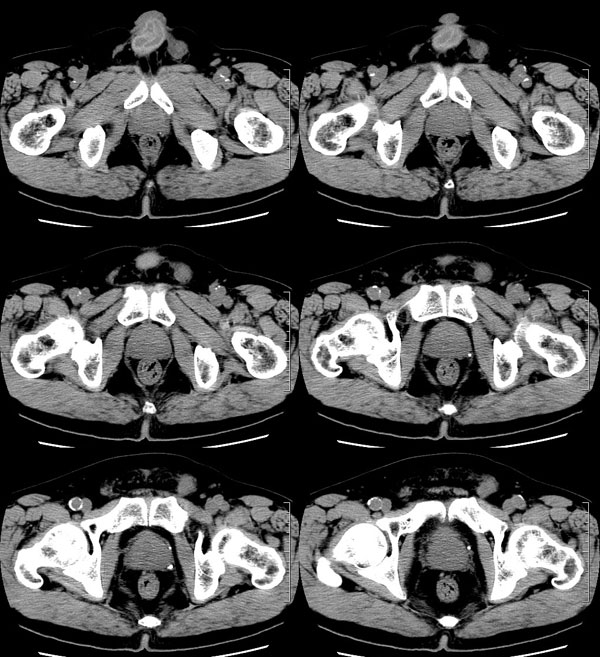

| 男性,69岁。自2个月前开始无意中发现左侧阴囊内一鸡蛋大小肿物,当时无伴疼痛等不适,未予重视。肿物逐渐增大,近段时间常伴左会阴部、腹股沟区牵扯不适,并于2周前在我院门诊行彩超检查提示“左侧附睾肿瘤可能,左侧睾丸鞘膜积液”。 专科检查:左侧阴囊肿大,其内可触及一鹅蛋大小肿物,表面光滑。肿物前部呈囊性感,后部质硬,按压无疼痛,无缩小,活动度良好。左侧睾丸未触及,透光试验(±)。                 王仕学发言:左侧睾丸见一密度不均肿块,边缘清楚,周围见水样密度影;考虑睾丸生殖细胞性肿瘤可能性大. 睾丸肿瘤占生殖系统肿瘤的3%-5%,占男性恶性肿瘤的0.5%-1.0%,其中生殖细胞性肿瘤占95%.睾丸肿瘤包括生殖细胞和非生殖细胞肿瘤两大类,前者占95%以上,后者不到5%.非生殖细胞肿瘤虽少见,但种类繁杂,主要有支持细胞、间质细胞和支持细胞-间质细胞瘤等功能性肿瘤,和间皮瘤、腺癌、横纹肌肉瘤、粘液性囊腺瘤、纤维上皮瘤、黑素神经外胚瘤、淋巴瘤等附属组织肿瘤。不同的病理类型的睾丸肿瘤发病率高峰不同,睾丸癌多发于35岁以前,精原细胞瘤发病高峰为30-35岁。精原细胞瘤约占睾丸肿瘤的60%,发病高峰在30-35岁。85%的患者睾丸有明显肿大,肿瘤局部侵犯力较低,肿瘤一般有明显界限。 手术:行“左侧附睾、睾丸、精索切除术”。 病理诊断:(左睾丸、附睾)肿物,为低分化腺癌。另送检(左精索远端)肿物,镜下亦为低分化腺癌。 免疫组化:ck(l)(++++)、cea(+++)、ca19-9(-)、psa(-)、plap(-)、p53(-)、vimentin(-)。 原贴地址:http://www.radinet.com.cn/forum_view.asp?forum_id=4&view_id=30707 |